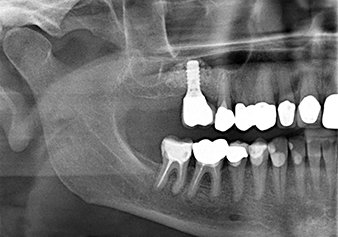

49-летняя пациентка, некурящая и не имеющая ничего примечательного в общей истории болезни, была направлена в нашу хирургическую стоматологическую клинику для хирургического удаления зуба 16 и последующей имплантации. После удаления зуба пациентка перенесла синусит в легкой форме, в результате чего мы сначала выждали шесть месяцев перед проведением операции. Остаточная высота кости при запланированном положении имплантата составляла 3-4 мм (рис. 1 и 2).

Для перемещения аугментационного материала в направлении верхнечелюстной пазухи атравматично, имплантат вводился очень медленно вручную (рис. 9). При этом мембрана еще раз выталкивалась в краниальном направлении. Через два месяца место операции зажило без раздражения. Через шесть месяцев рентгеновский контроль показал значительное увеличение помутнения, что свидетельствует об оссификации (рис. 10). Протезирование было проведено металлокерамической коронкой.